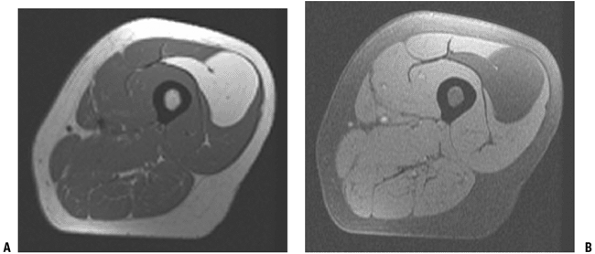

MRI is the imaging modality of choice in

the diagnosis and therapeutic planning of soft tissue tumors. It is

superior to other imaging modalities in determining size, location, and

anatomic relationships to neurovascular structures in multiple planes. -

In general, most tumors demonstrate dark signal on T1-weighted images and bright signal on T2-weighted images (Fig. 2-5).

![]() |

Figure 2-5 A typical MRI appearance of a soft tissue sarcoma in the arm. (A) The mass displays dark signal on the T1-weighted image, which is isointense with the adjacent muscle. (B)

On the T2-weighted image, the mass displays bright signal relative to the surrounding normal tissues. On both sequences, there is considerable heterogeneity, which is more obvious on the T2 image. |